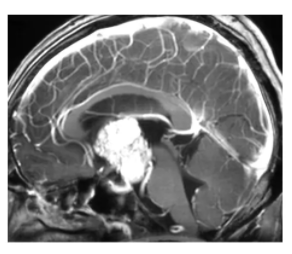

儿童恶性肿瘤主要分为白血病和实体瘤两大类。以18岁为年龄划分,儿童的恶性肿瘤,叫母细胞瘤,比如常见的髓母细胞瘤、神经母细胞瘤、肾母细胞瘤、肝母细胞瘤。